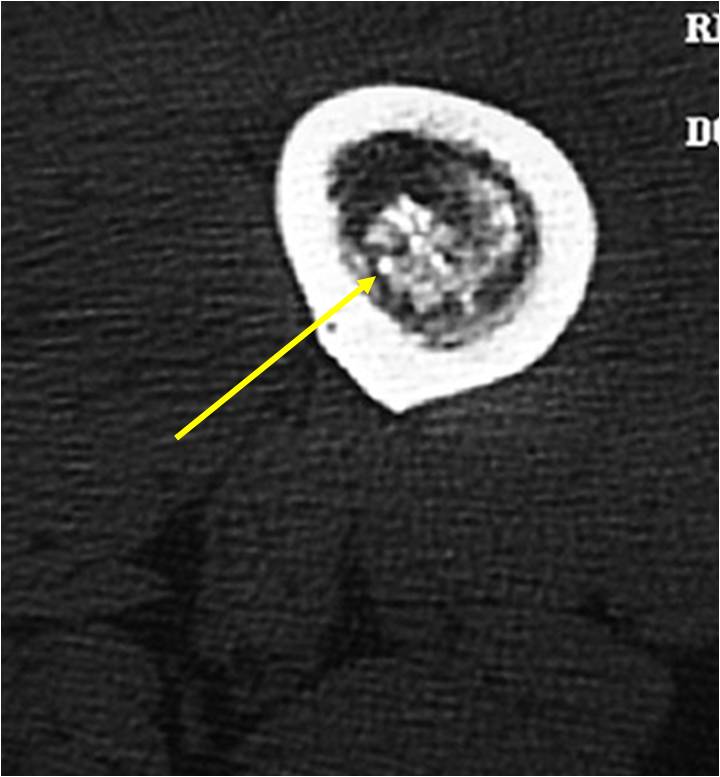

MRI:

- Lobulated margin (Lobular Growth Pattern)

- T1 Weighted Images: Intermediate Signal Intensity

- Calcifications will be low signal

- T2 Weighted Images: High Signal Intensity

- High water content shows as high signal on T2 weighted images

- Marked increased intensity long TR images

- Calcified chondroid – low intensity all sequences

- There should never be any cortical destruction nor a soft tissue component. If this exists then the tumor must be a chondrosarcoma.

- Endosteal scalloping and cortical expansion is acceptable for phalangeal tumors. In most benign long bone cartilage tumors there is minimal endosteal scalloping but there should be no cortical expansion nor thickening. There should be no cortical destruction and no soft tissue component associated with an enchondroma. Cortical destruction, periosteal thickening, cortical expansion and a soft tissue component indicates a chondrosarcoma of the long bone.